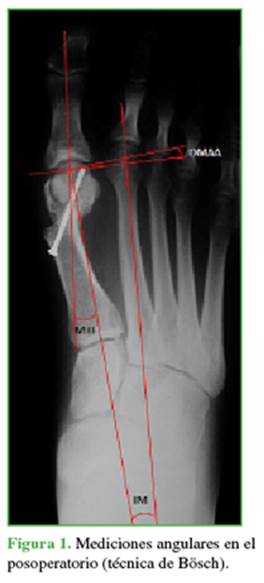

Las mediciones radiográficas después de la cirugía estuvieron a cargo de cirujanos que no habían operado al paciente (Figuras 1 y 2). De esta manera, se evaluó la pérdida o no de la corrección en ambas técnicas quirúrgicas. Todas las imágenes fueron digitales, con un programa computarizado (MB Rouler® versión 4.0), se calcularon los siguientes parámetros: a) el ángulo MTF, b) el ángulo IM usando la técnica de medición de Miller16 y c) el ángulo AMD, según la técnica mencionada por Deenik y cols.17

1)        El promedio de corrección para los ángulos MTF, IM y AMD fue de 20,79°; 8,14°; y 8,65° a las 6 semanas; y 20,22°; 7,74° y 8,26° a los 6 meses, respectivamente.

2)        Las diferencias entre el ángulo IM preoperatorio y a las 6 semanas de la cirugía, y entre el preoperatorio y a los 6 meses de la cirugía fueron estadísticamente significativas (ambas p <0,005). La relación entre el ángulo IM a las 6 semanas y a los 6 meses de la cirugía no fue estadísticamente significativa (p = 0,033). Esto muestra que no hubo pérdida de corrección significativa entre las 6 semanas y los 6 meses del posoperatorio.

3)       Las diferencias entre el ángulo MTF preoperatorio y a las 6 semanas de la cirugía; y entre el preoperatorio y a los 6 meses de la cirugía fueron estadísticamente significativas (ambas p <0,005). La relación entre el ángulo IM a las 6 semanas y a los 6 meses de la intervención no fue estadísticamente significativa (p = 0,34). Esto muestra que no hubo pérdida de corrección significativa entre las 6 semanas y los 6 meses posoperatorios.

4)        En cuanto a la corrección del AMD, la relación entre el preoperatorio y a las 6 semanas y a los 6 meses de la cirugía fue significativa en ambas mediciones (p <0,005). La pérdida de corrección entre las 6 semanas y los 6 meses posoperatorios no fue significativa (p = 0,50).